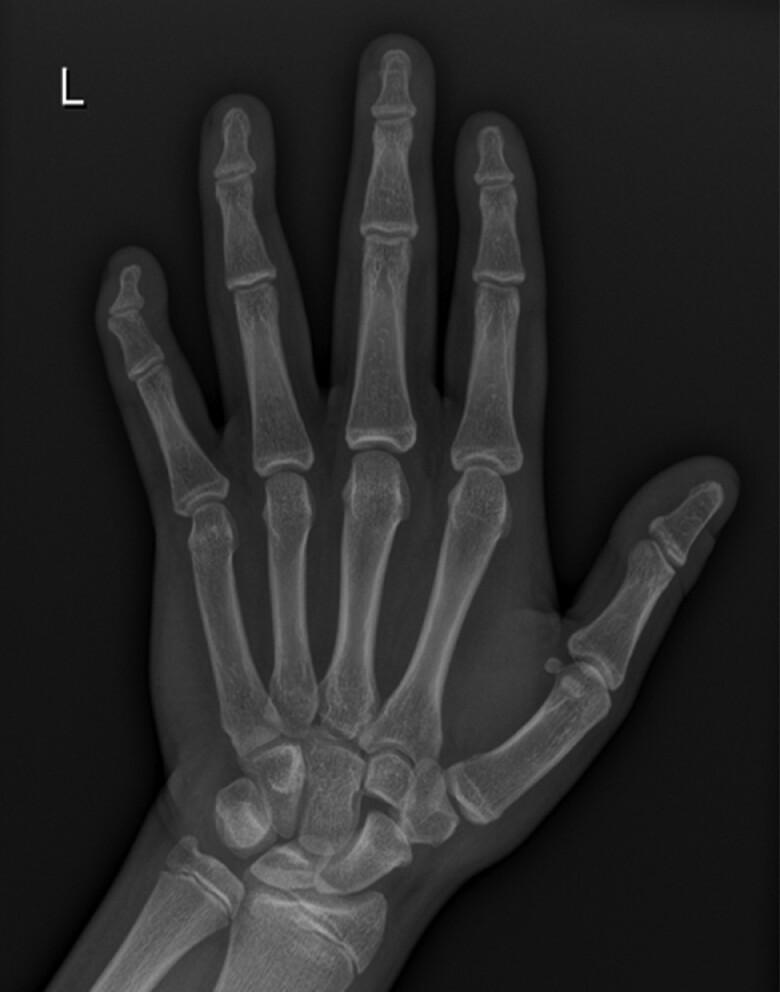

variants were recently described in 1% of patients not known to have pseudohypoparathyroidism/inactivating PTH/PTHrP signalling disorder 2 in the UK Genetics of Obesity Study. We describe a new missense variant, c.791A > C, p.(Asp264Thr), in a family with obesity, hyperphagia and mild PTH resistance. A 6-year-old female (body mass index +4.3 SD score [SDS], height +1.9 SDS) presented with hyperphagia and obesity from age 3 years. She had subtle brachydactyly, macrocephaly, and mildly delayed development. The 12-year-old brother (height +2.1 SDS, body mass index +2.9 SDS) had hyperphagia, obesity, mildly delayed development, and autism. He had subtle brachydactyly, as did the affected mother. We assessed the functional effect of the mutant, measuring cAMP production in cells transfected with wild type and mutant GNAS after ligand stimulation. Cells with the mutant GNAS showed impaired cAMP generation through melanocortin receptor 4, GH releasing hormone receptor, and PTH receptor. These cases demonstrate the clinical heterogeneity of monogenic disease, suggesting a need to test for PHP1A in children with obesity even without classical signs of PHP1A.

在英国肥胖遗传学研究中,最近在1%的无假甲状旁腺功能减退症/失活性甲状旁腺激素/甲状旁腺激素相关蛋白信号传导障碍2的患者中发现了变异体。我们在一个患有肥胖症、食欲亢进和轻度甲状旁腺激素抵抗的家庭中描述了一种新的错义变异体,即c.791A>C,p.(Asp264Thr)。一名6岁女性(体重指数+4.3标准差评分[SDS],身高+1.9 SDS)从3岁起就出现食欲亢进和肥胖。她有轻微的短指畸形、巨头畸形和轻度发育迟缓。12岁的哥哥(身高+2.1 SDS,体重指数+2.9 SDS)有食欲亢进、肥胖、轻度发育迟缓和自闭症。他有轻微的短指畸形,患病的母亲也有。我们评估了该突变体的功能效应,在配体刺激后测量了用野生型和突变型GNAS转染的细胞中cAMP的产生。携带突变型GNAS的细胞通过黑皮质素受体4、生长激素释放激素受体和甲状旁腺激素受体显示出cAMP生成受损。这些病例证明了单基因疾病的临床异质性,表明即使没有假甲状旁腺功能减退症1A型的典型体征,肥胖儿童也需要检测假甲状旁腺功能减退症1A型。